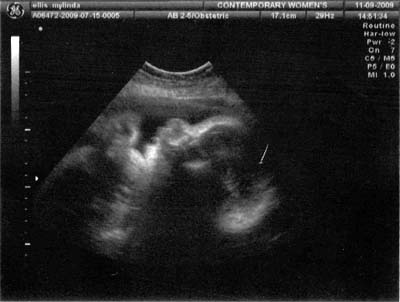

This was a type 2 ultra sound it is older but my printer would not scan. Kodak was nice enough to send me another one with the same problem. However after getting two new  printers and finally upgrading (at the expense) to a different model we have a working printer.

I went to the Dr.'s yesterday and these are the latest photos. I am not a real big fan of the 3D ultra sounds as the baby look alienish but thought I would share them anyway.

How great it is to live in a time where we have all the modern technology to be able to see photos of the unborn babies. He is doing well and weights 4 1⁄2 lbs. He is very active and I'm sure will give me a run for my money. Still don't have a name but I think we will decide when we see him. Hope everyone is doing well. Love ya, Zeke, Mylinda, Lauren and the boy.